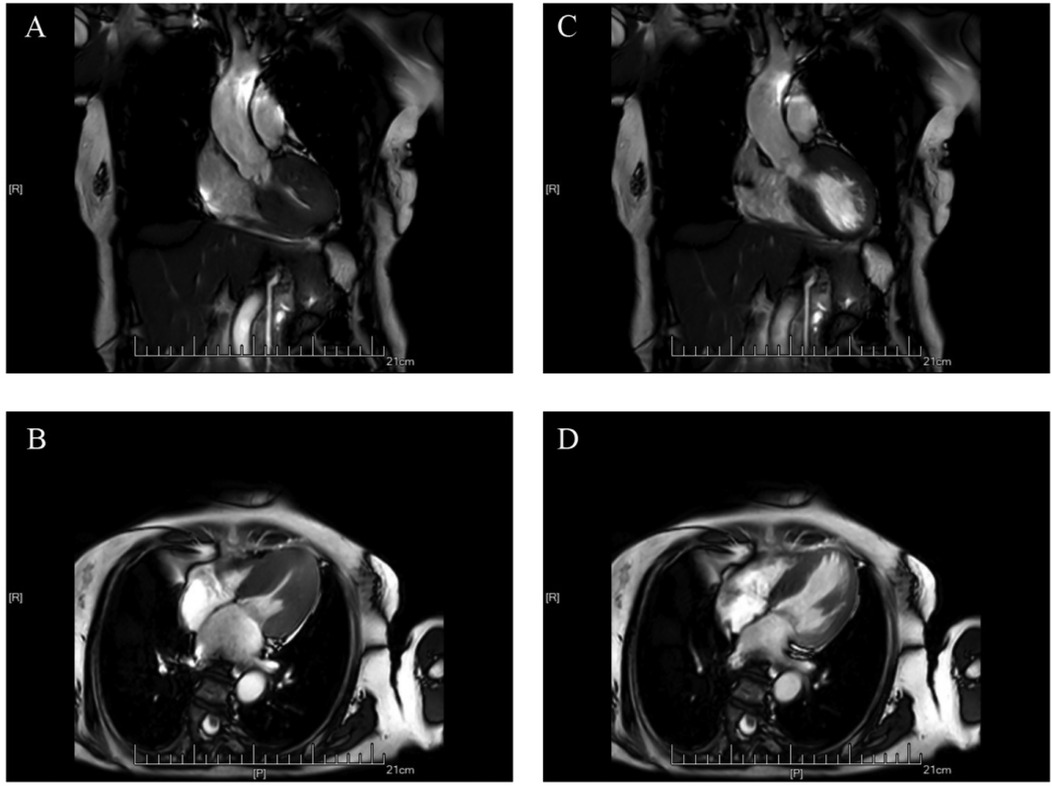

Cardiac magnetic resonance imaging (CMR) demonstrated patchy mid-septal delayed gadolinium enhancement without abnormal myocardial perfusion (Figure 3). A 24 h ambulatory ECG (Holter) revealed occasional ventricular and atrial premature beats, as well as brief episodes of atrial tachycardia (Figure 4). Coronary angiography identified scattered plaques in the proximal left anterior descending artery (LAD) with a maximal stenosis of 30% and approximately 20% stenosis in the mid-proximal right coronary artery (RCA), without significant obstruction in other coronary segments.

Figure 3

MRI scans of the human chest and heart viewed in coronal and axial slices. Images A and C display coronal views, while images B and D show axial views. Each scan highlights the cardiovascular structures and adjacent tissues with varying levels of contrast.

Figure 3. Cardiac MRI scans showing hypertrophic cardiomyopathy. (A,C) Coronal views; (B,D) Axial views.